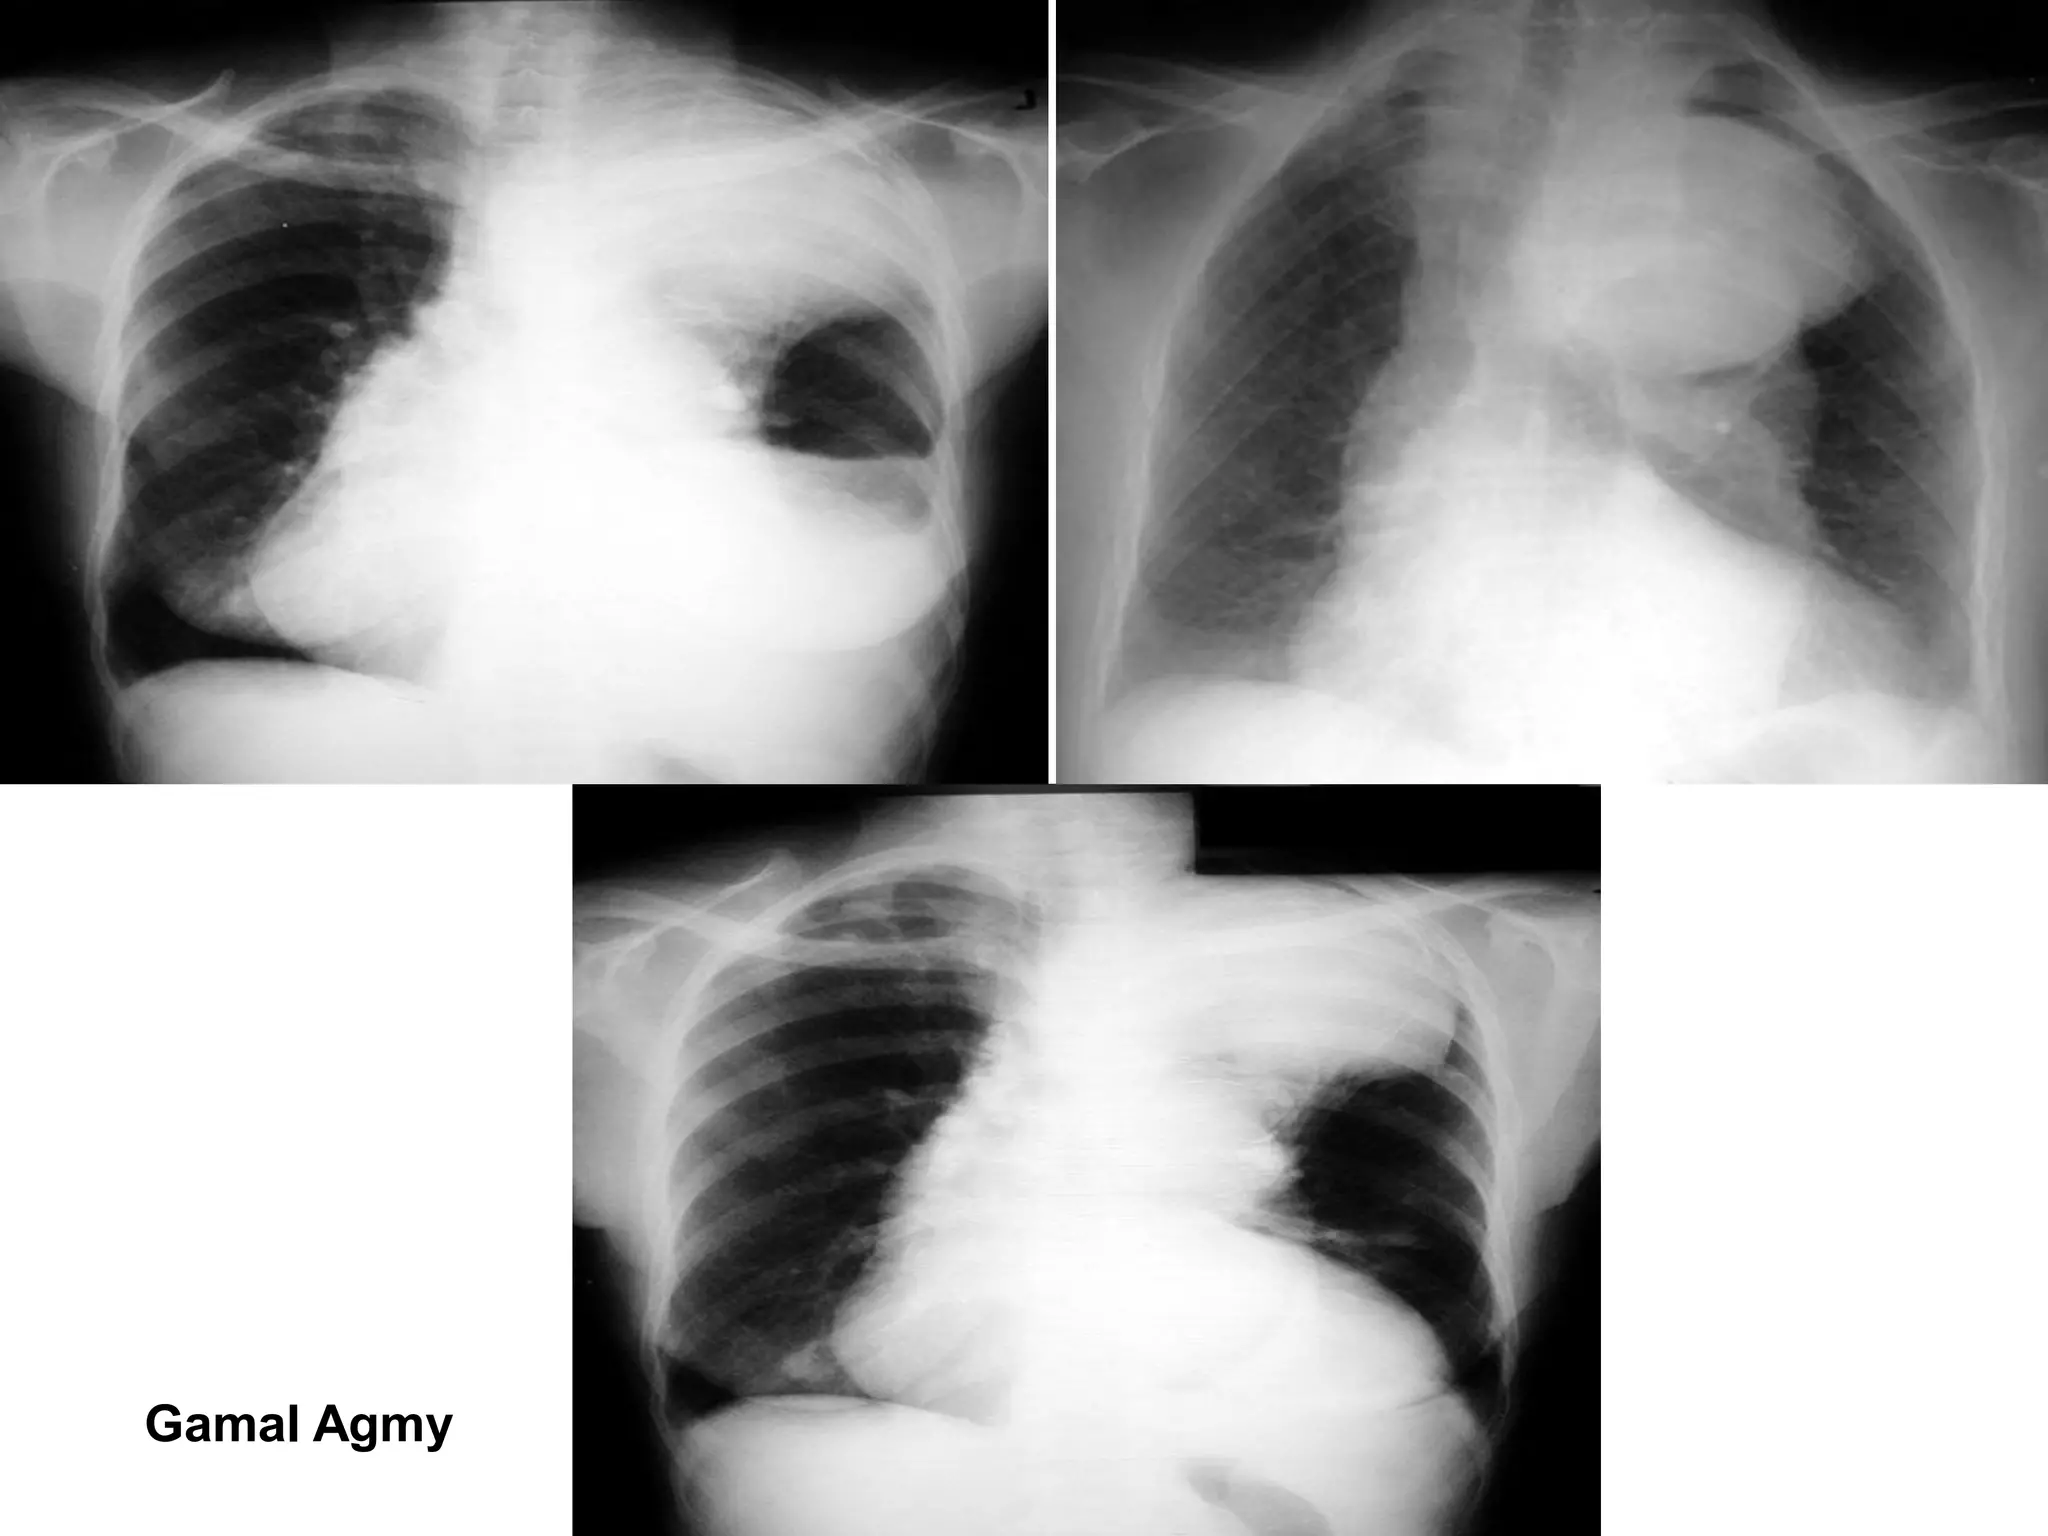

Imaging of pulmonary vascular lesions